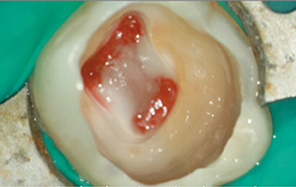

Gil Tirlet introduira, quant à lui, un bouleversement dans le monde des restaurations dentaires et du concept mécanique et délabrant des prothèses conjointes conventionnelles, lors de sa conférence.

Il exposera les techniques alternatives à la pose de couronnes lorsque la dent est très abîmée avec des concepts de dentisterie contemporaine. Pour cela, il s’attachera à développer les concepts de biomimétique et de bioémulation en prenant la dent comme « Maître » modèle et en mimant au plus proche le comportement physiologique de la dent.

- La dent naturelle : un maître mot pour la dentisterie contemporaine

par Gil Tirlet

La plus-value tient en deux mots : nouveautés et révolutions. Les concepts, présentés par trois grands noms de la profession, sont révolutionnaires voire avant-gardistes dans le mode de la dentisterie. Pour ne donner qu’un exemple, l’intervention de David Nisand va à l’encontre des idées reçues en implantologie. Quant à Stéphane Simon et Gil Tirlet, ils repensent les techniques actuelles.

Ils expliqueront comment conserver la pulpe voire la façon dont le praticien peut la régénérer au lieu de la remplacer. Les techniques adhésives qui dépassent largement ce que nous avons vu jusqu’à maintenant, permettent la restauration de délabrements partiels, mais aussi de grands délabrements sur des dents dépulpées ou non, mais avec des pertes de substances importantes.

Si toutes les conférences seront de haut vol, elles ne seront jamais inaccessibles. Pour illustrer des concepts complexes, les conférenciers présenteront des cas cliniques réels et de tous les jours. Inscrire ces nouveautés dans leur traduction clinique, tel est l’un des objectifs de cette séance.

De plus, tous les clichés illustrant les conférences seront présentés en haute définition. Il faut s’attendre à une projection de photos exceptionnelles ! À la fin de chaque conférence, comme chaque année, des questions et débats seront organisés entre les conférenciers et les congressistes.